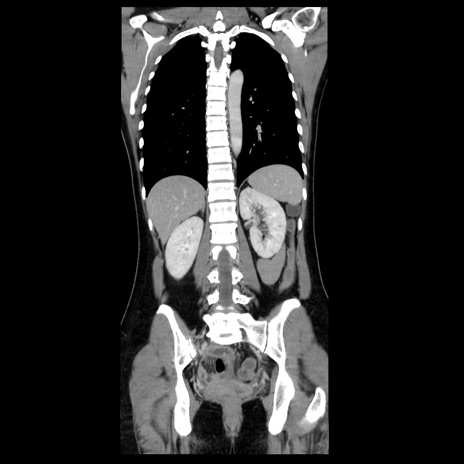

症例39(冠状断像)

【症例】40歳代女性

【主訴】上下腹部痛

【現病歴】2日目から下腹部痛あり。夜間は痛みで眠れなかった。昨日より上腹部痛と下痢が出現。臥位で痛みは軽快したため、休んでいた。本日になって臥位でも立位でも痛みが強くなってきたため救急要請。

【既往歴】子宮内膜症

【身体所見】部:平坦・軟、左上下腹部に圧痛あり、反跳痛あり。

【データ】WBC 21800、CRP 26.78

CT